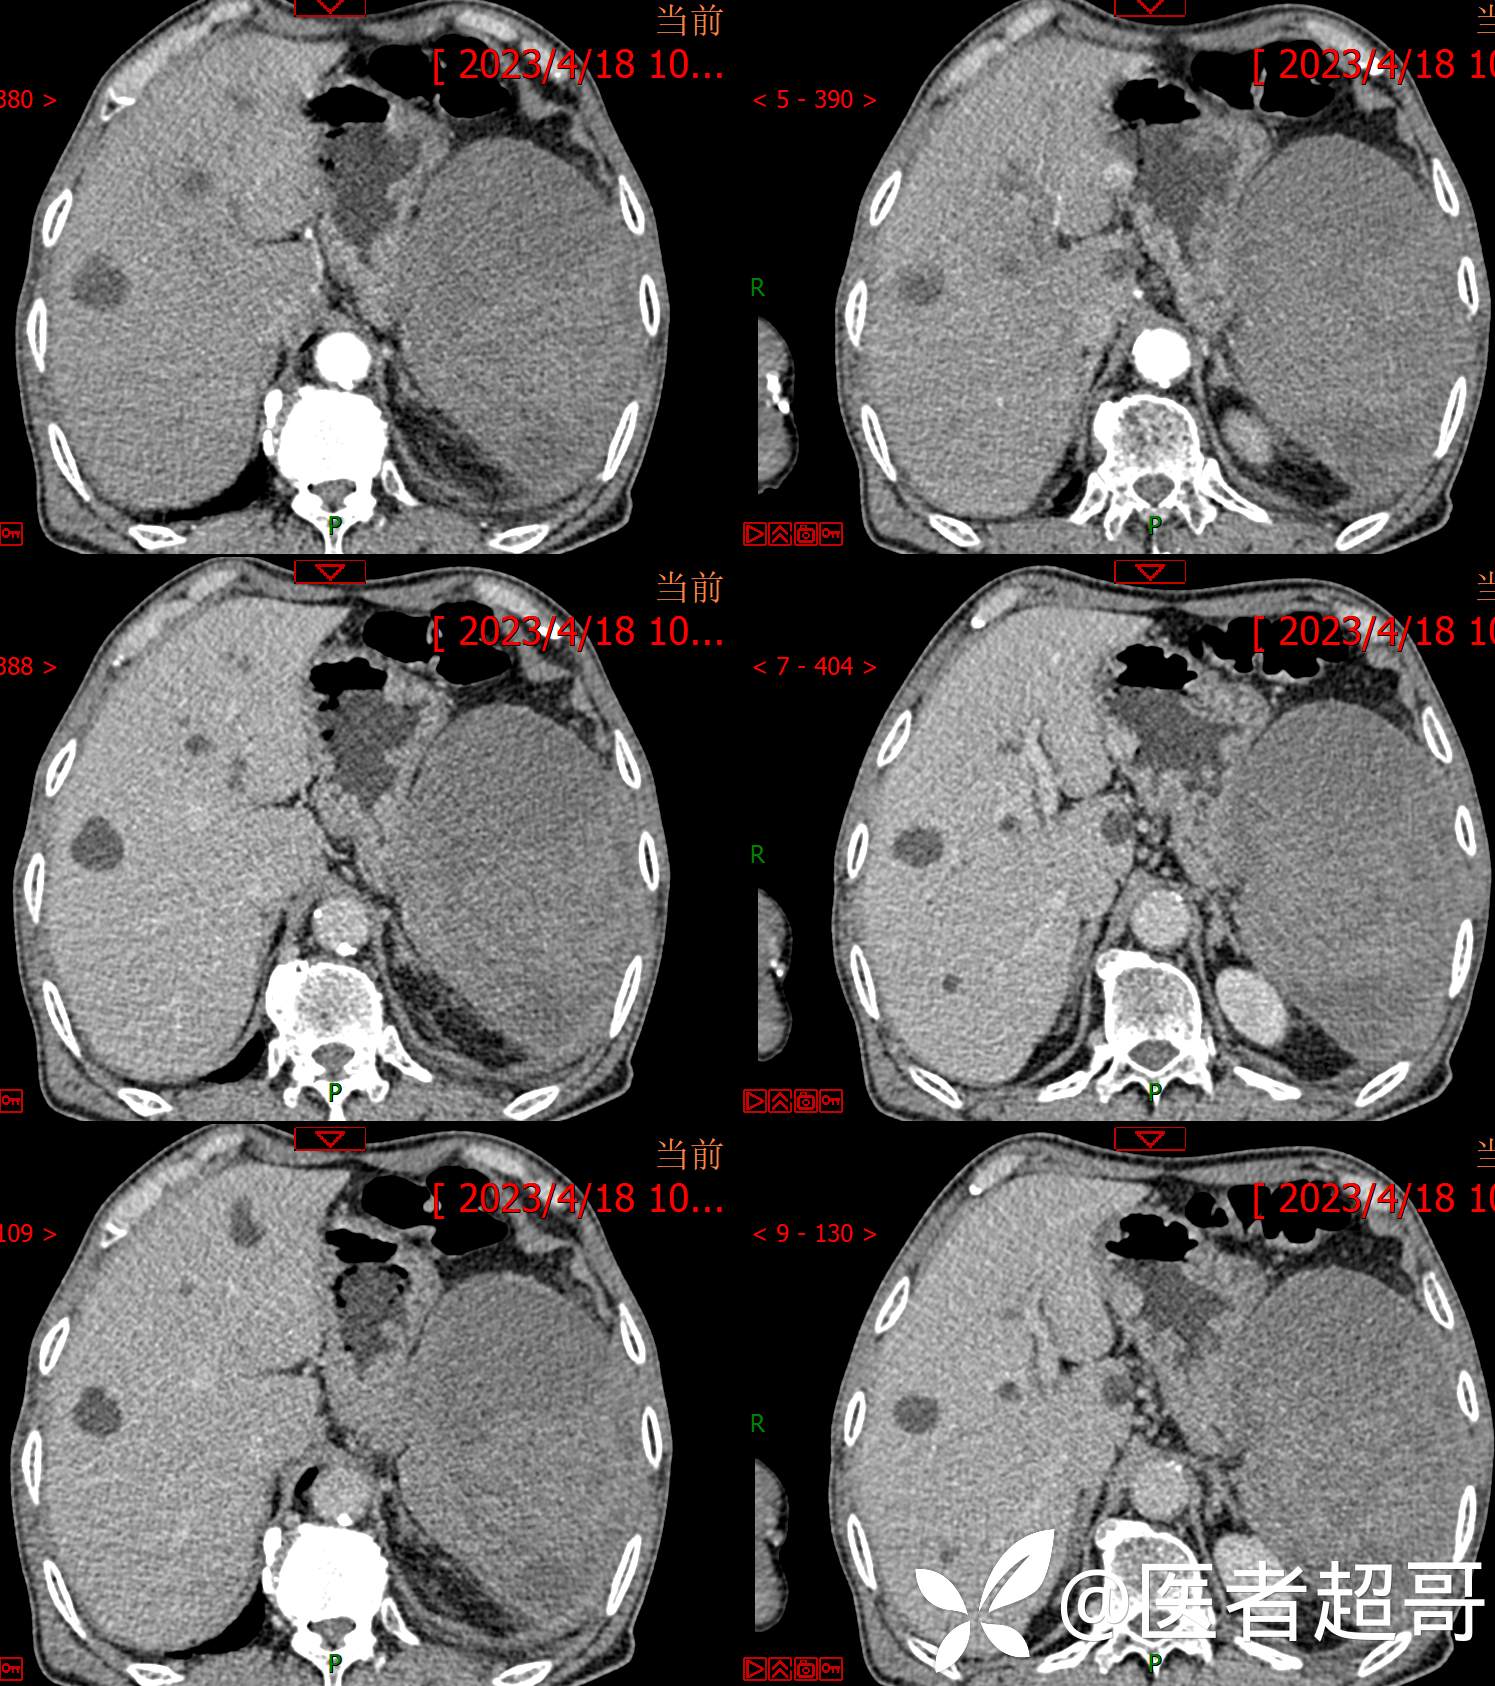

一波三折,术前确诊,术后肝脏广泛爆发,原因在何?让我们一探究竟!欢迎留言分析~~~

简要病史:左侧胸部疼痛不适5天就诊,临床初步诊断“肋软骨炎”。

术后三个月复查CT、MRI表现: